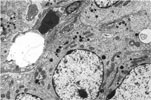

110. Electron Micrograph

-Pulmonary Alveolar Type II Adenoma

111. Electron Micrograph